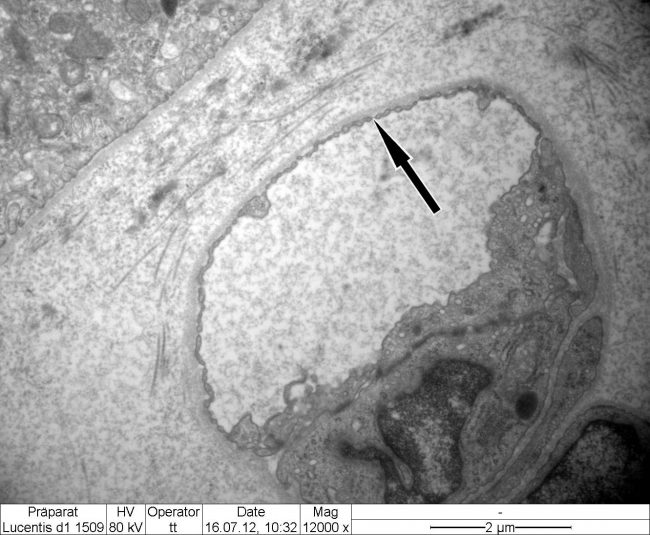

- Electron Microscope

- Electron Microscope